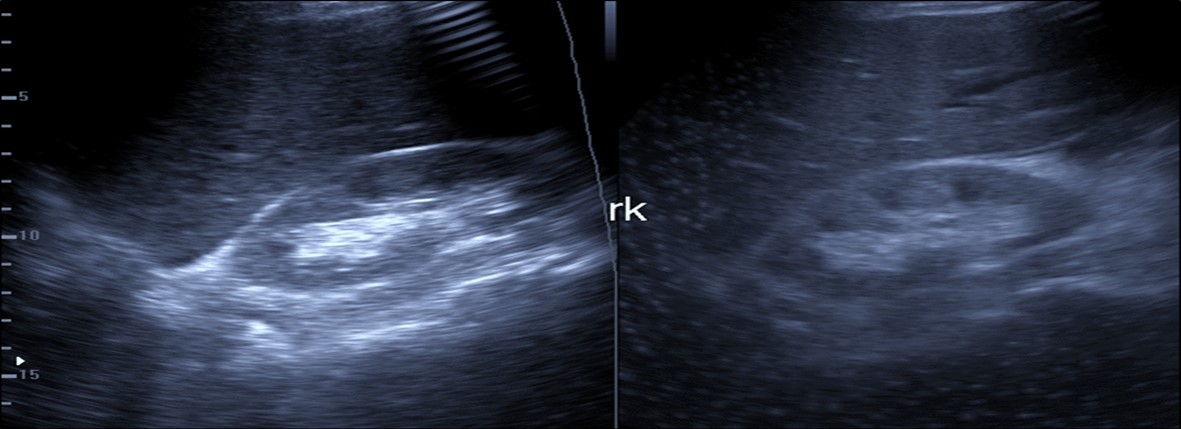

Abdominal ultrasound may revealed any of the followings:-Mild hepatomegaly with echogenic parenchyma and ascites in cases with hepatic impairment (Figure 4, Figure 5) ,thick walls of gall bladder with mildly dilated Common bile duct suggesting of biliary stasis and cholecystitis (Figure 6) .Abnormal renal echogenicity (Figure 7), suprarenal gland enlargements with heterogeneous texture ,splenic wedge shape area of hypoechogenicity ,thickened walls of bowel mainly the rectosigmoid region ,dilated bowel loops with free peritoneal fluid, and gases in the bowel wall with mesenteric and portal vein gases suggesting of bowel wall infarction13.

Figure 7.Patient with Covid-19 showing an echogenic kidney (rk) by ultrasound.

Patient with Covid-19 showing an echogenic kidney (rk) by ultrasound.